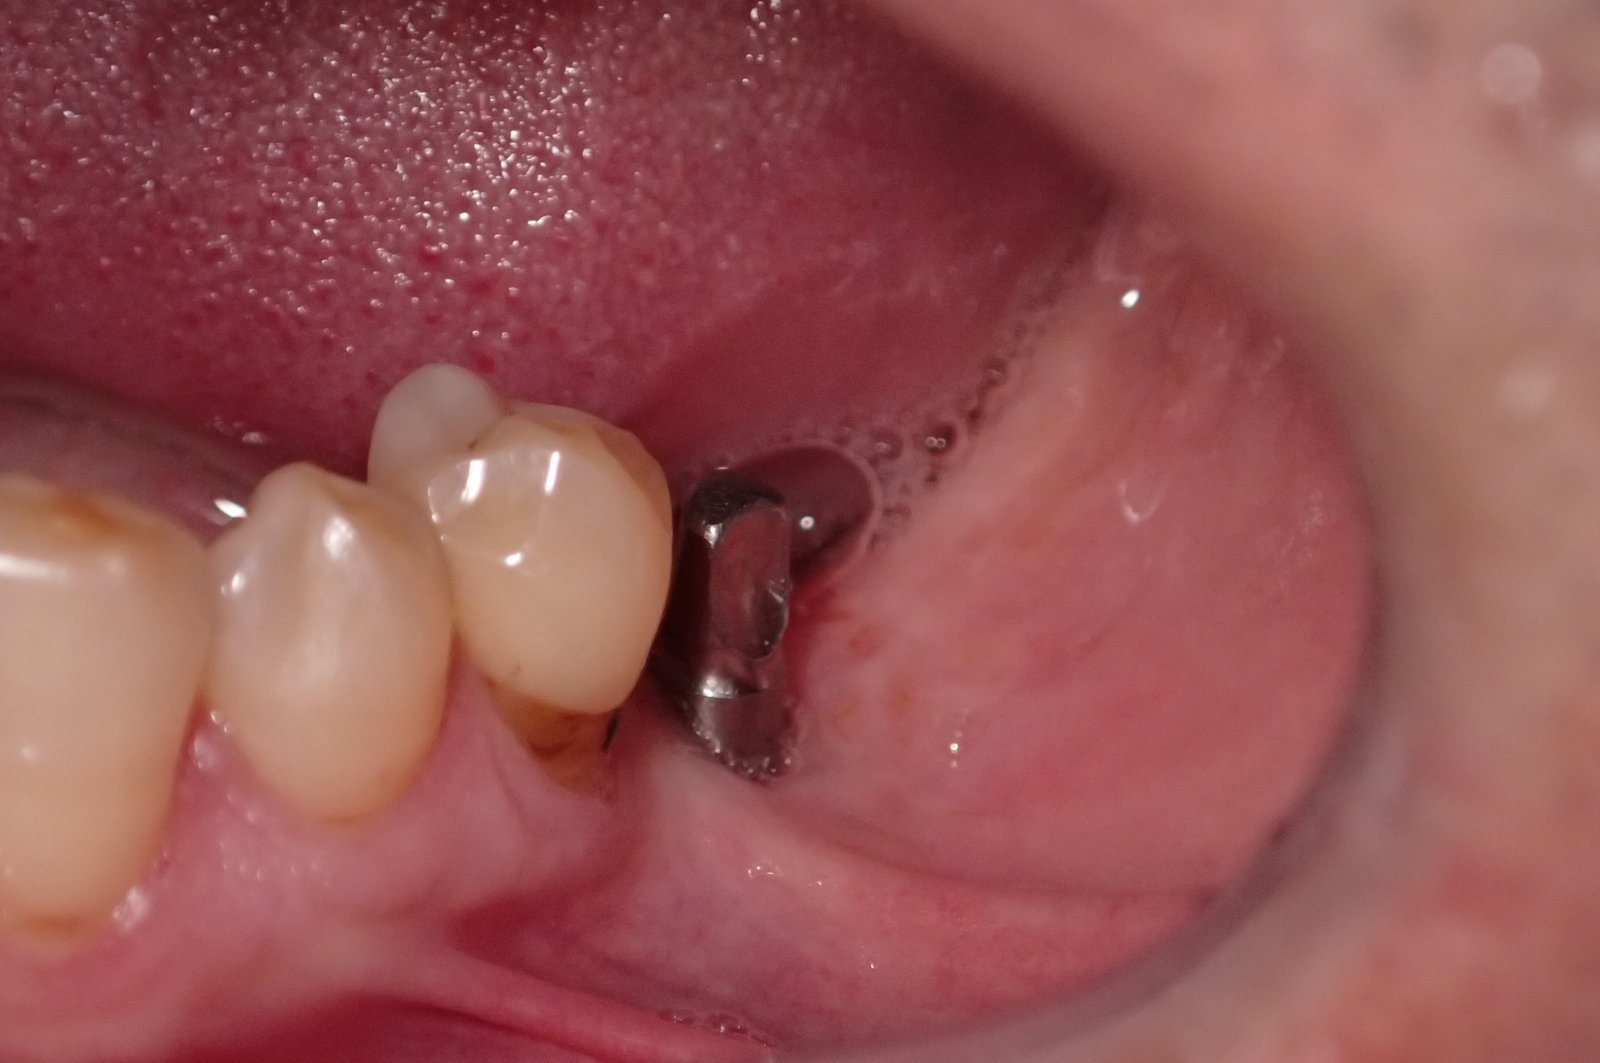

Buenas tardes, me llega para rehabilitar este implante y la señora viene de idental, el pilar se lo han puesto en otra clínica, gracias de antemano. Saludos.